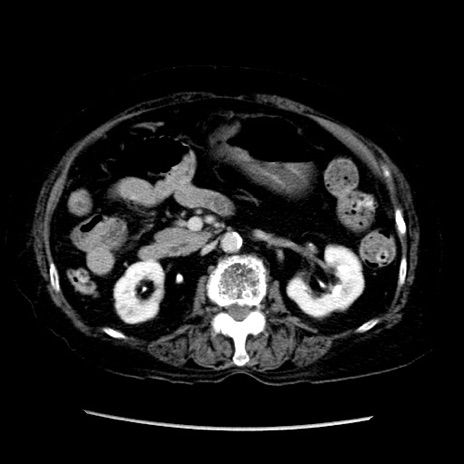

症例14(横断像)

【症例】 90歳代女性

【主訴】 腹痛・嘔吐

【現病歴】今朝から左側腹部痛を認めた。 経過観察していたが、嘔吐を認めたため来院。

【既往歴】 子宮癌術後

【身体所見】 意識清明、BP 127/54mmHg、P 98bpm Sp02 95%(RA)、BT 35.8°C、腹部平坦・軟腸ぜん動音聴取良好、右下腹部圧痛(+) 反跳痛なし

【データ】WBC 9800、CRP 0.46